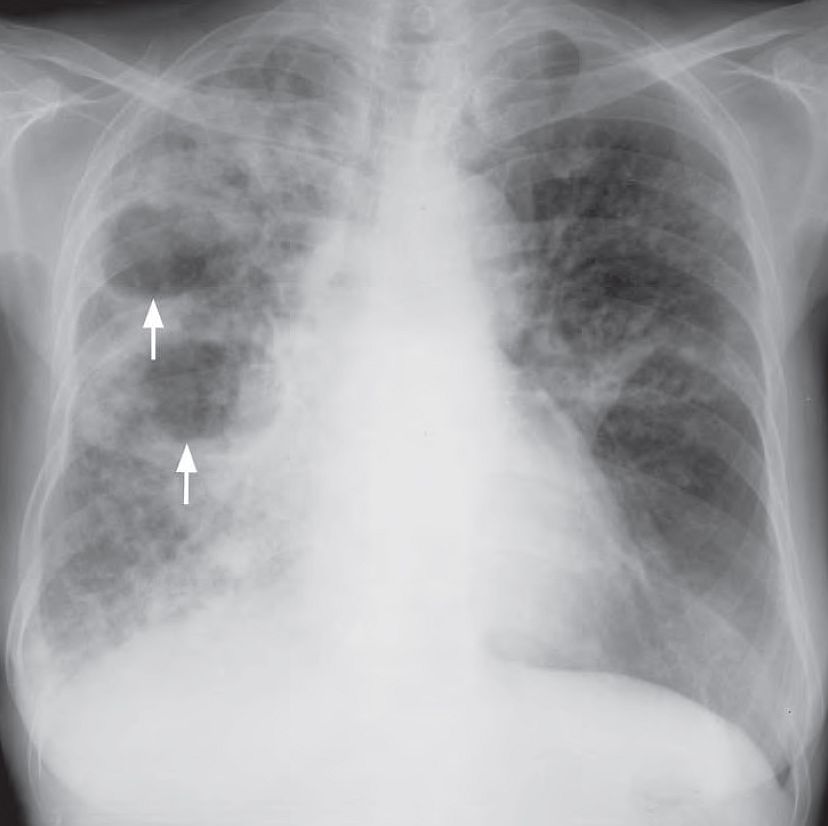

A 45-year-old woman with poorly controlled diabetes mellitus, presented with productive cough for 1 month. She also noticed low grade fever, night sweating and weight loss during this period.

Examination of the chest showed a dull percussion note, decreased air entry and coarse crepitations in the right upper zone. Laboratory investigations revealed raised ESR, normal white cell count and a CXR was performed.

What radiological abnormalities can you identify and what is the likely diagnosis ?